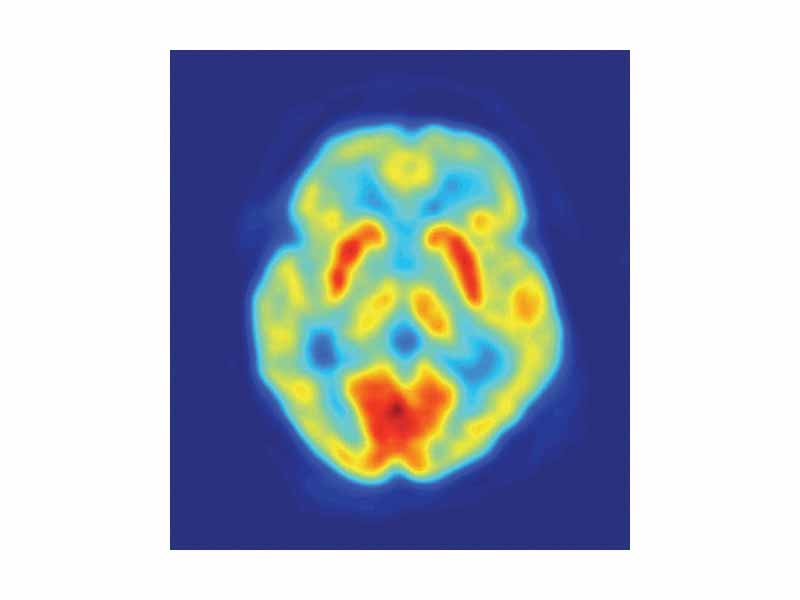

PET Image of the human brain showing energy consumption